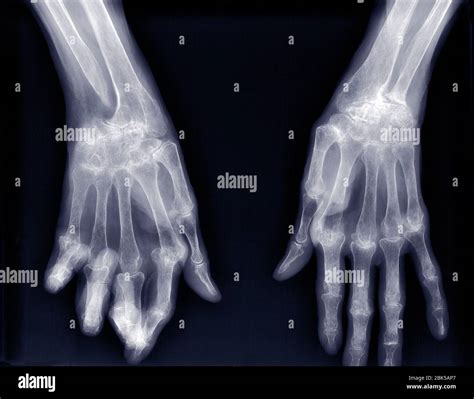

• Arthritis Assessment: Identifying the loss of joint space, bone spurs, or cartilage erosion associated with osteoarthritis or rheumatoid arthritis.

• Congenital Abnormalities: Evaluating skeletal development issues or anatomical variations present from birth.

After your physician receives the report, they will schedule a follow-up appointment to discuss the results with you. Depending on what the X-ray of hand reveals, your treatment plan could range from a simple splint or cast for a minor fracture to physical therapy for overuse injuries, or medication management for chronic arthritic conditions.

• Track the progression of degenerative diseases to adjust treatments accordingly.